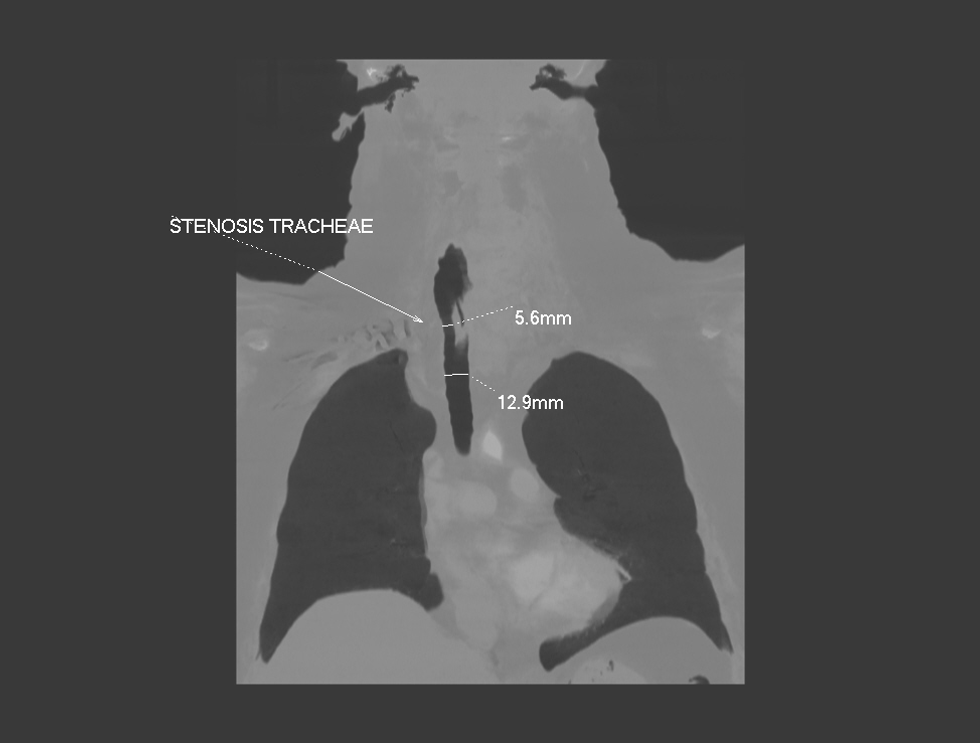

Patologjia e gjëndrës tiroide mund të manifestohet në formën e ndryshimeve në strukturën ose në funksionin e saj. Në grupin e sëmundjeve të gjëndrës tiroide përfshihet edhe gusha, e cila zakonisht manifestohet si rritje e vëllimit të gjëndrës tiroide në pjesën e përparme të qafës.

Gusha është pa dhimbje, por nëse rritet shumë, mund të shkaktojë vështirësi në gëlltitje, ndryshime në zë, kollë dhe vështirësi në frymëmarrje. Në këtë rast, e vetmja zgjidhje për trajtim është ndërhyrja kirurgjikale.

Në Klinikën Zhan Mitrev, është diagnostikuar dhe e mënjanuar në mënyrë kirurgjikale gusha/struma me përmasa të mëdha tek një paciente me vështirësi në frymëmarrje dhe gëlltitje.